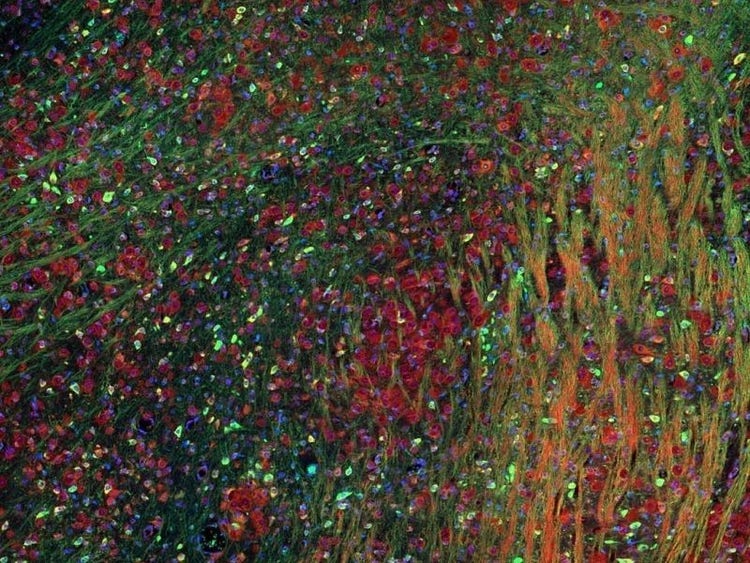

Fluorescence imaging of a mouse brain

Jedes dieser Bilder sieht aus der Nähe anders aus, aber sie fügen sich zu einem Bild eines Mäusegehirns zusammen, das mit Fluoreszenzbildgebung aufgenommen wurde.

Der britische Wissenschaftler Sir George G. Stokes beobachtete zum ersten Mal, dass das Mineral Flussspat fluoresziert, wenn es mit ultraviolettem Licht beleuchtet wird, und prägte den Begriff „Fluoreszenz“. Stokes fand heraus, dass das fluoreszierende Licht eine größere Wellenlänge hat als das Anregungslicht, ein Phänomen, das heute als Stokes-Verschiebung bekannt ist. Die Fluoreszenzmikroskopie ist eine hervorragende Methode zur Untersuchung von Materialien, die entweder in ihrer natürlichen Form (Primär- oder Autofluoreszenz) oder nach Behandlung mit fluoreszierenden Chemikalien (Sekundärfluoreszenz) fluoreszieren können.